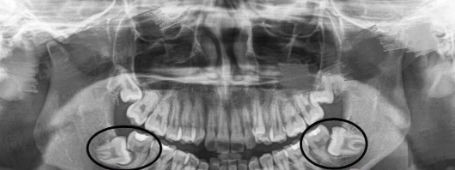

从智齿的生长方面来说:个体差异很大,有的人二十岁之前,有人四十、五十岁才长,有人终生不长,这都是正常的。而且四颗智齿也不是都必然长全,某些人的智齿可能只长一至两颗,有的智齿甚至长到一般就不再生长了,这种情况称为指出阻生即阻生齿。

1、位置不正,常见于下颌智齿:智齿向前生长挤压到邻牙,此外,向后、向舌侧、向颊侧、甚至向下长也都可能产生危害。智齿生长方向不正常,通常会导致智齿与相邻的磨牙间出现缝隙或者凹槽,极易嵌塞食物残渣,长时间清理不干净,相邻磨牙将发生龋齿、牙髓炎、根尖炎等。